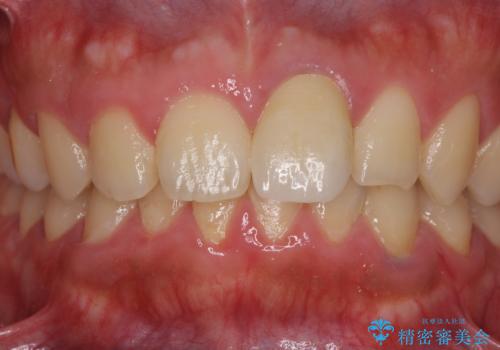

レントゲン写真より、歯の中の神経組織が失活していることが分かったため、根管治療、ファイバーコアによる土台築製を行い、オーダーメイドタイプのオールセラミッククラウンにて補綴することとしました。

人目を気にすることなく話ができるようになり、患者様には大変満足していただきました。